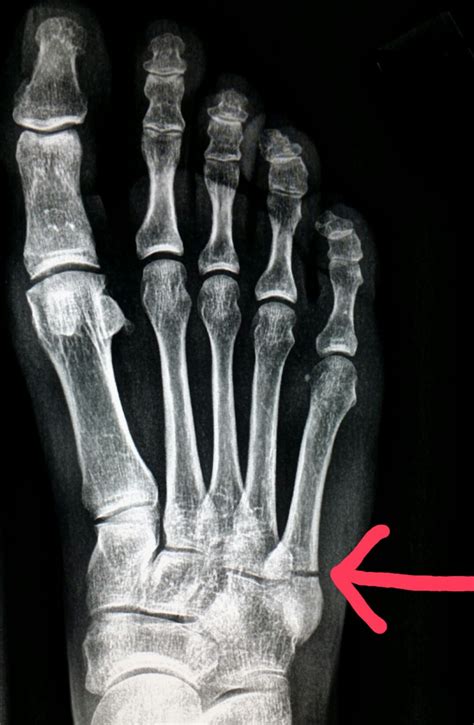

• Imaging Tests: X-rays are the most common imaging test used to diagnose fractures. However, hairline fractures may not always be visible on initial X-rays. In such cases, additional imaging tests such as MRI or CT scans may be required.

A hairline fracture, also known as a stress fracture, is a thin crack in the bone. In the case of a hairline fracture ankle, this crack typically occurs in one of the three bones that form the ankle joint: the tibia, fibula, or talus. These fractures are often caused by repetitive stress or a sudden impact, such as twisting the ankle or landing awkwardly after a jump.

Diagnosing a hairline fracture ankle involves a combination of physical examination and imaging tests. Your healthcare provider will likely perform the following steps: